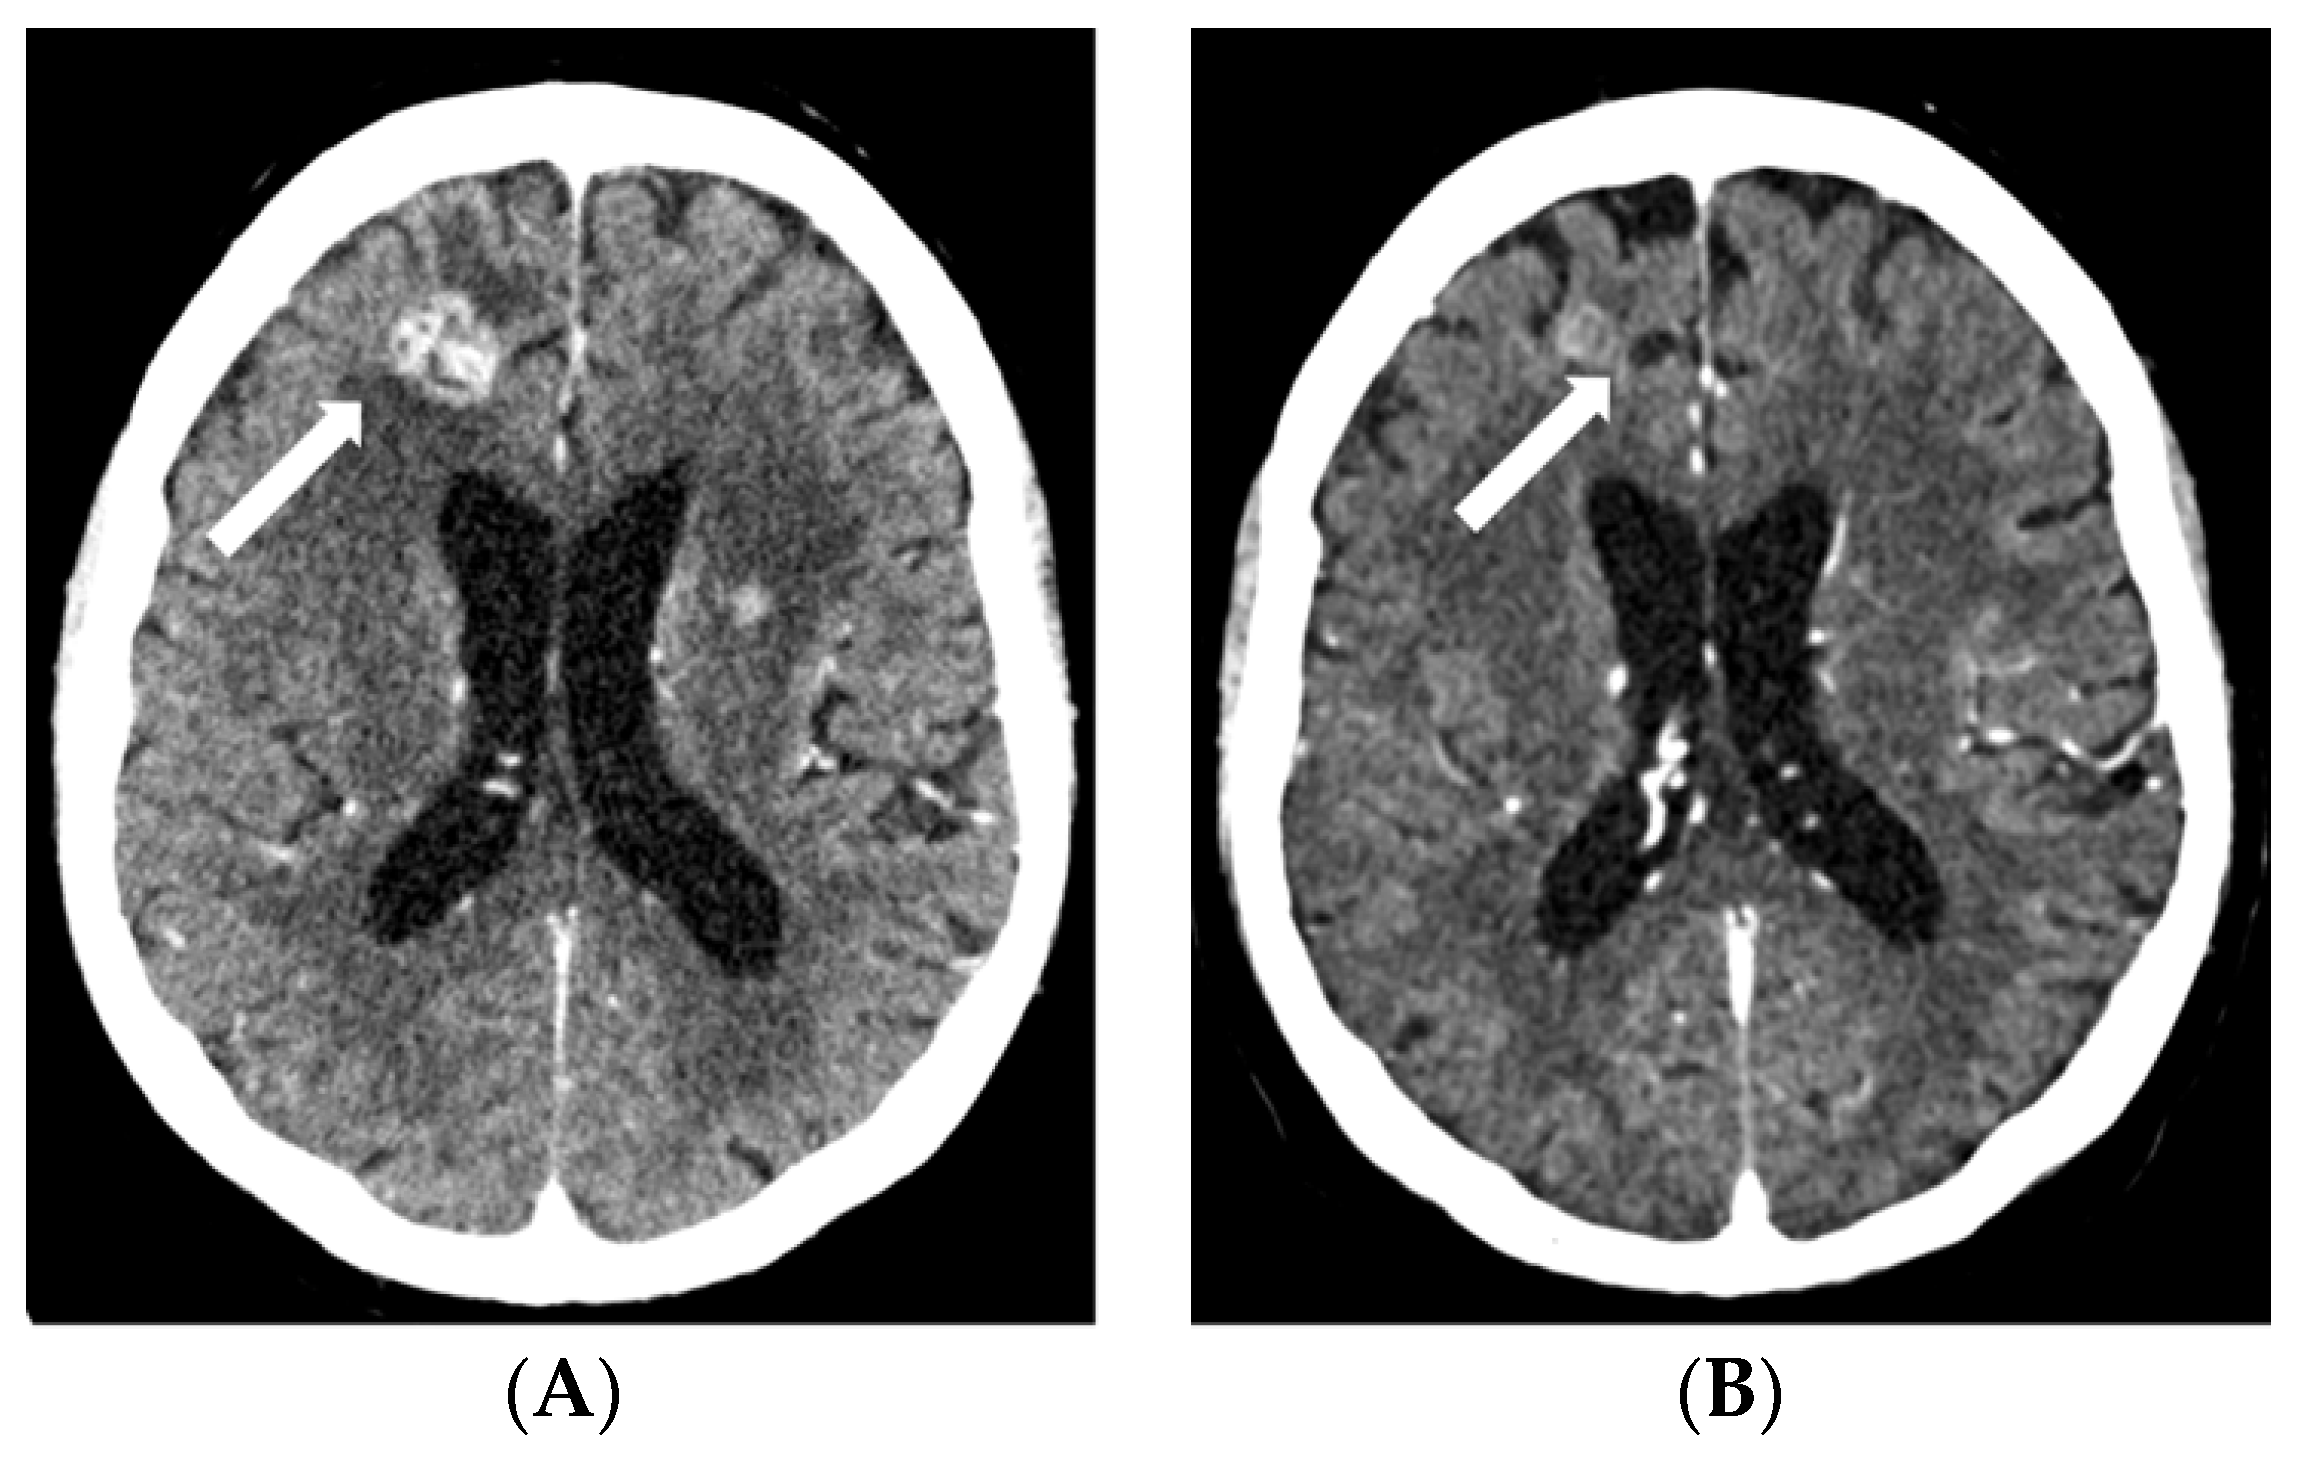

2.3. Case 3